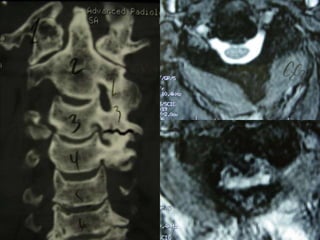

Schmorl Node